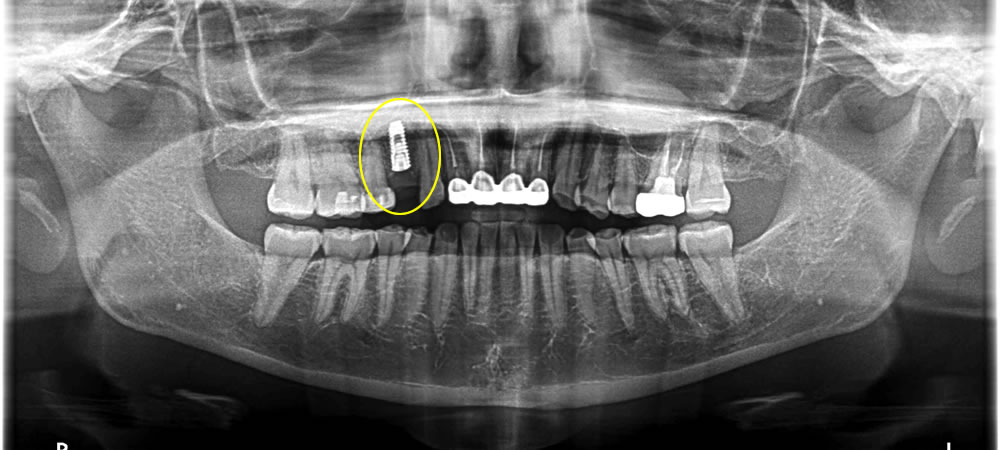

上部構造の装着・治療完了

インプラントと顎骨がきちんと結合していることを確認後、上部構造を装着して治療完了です。治療後は固いものも問題なく噛むことができ、何より見た目が普通の歯とほぼ変わらず、大変満足していただくことができました。